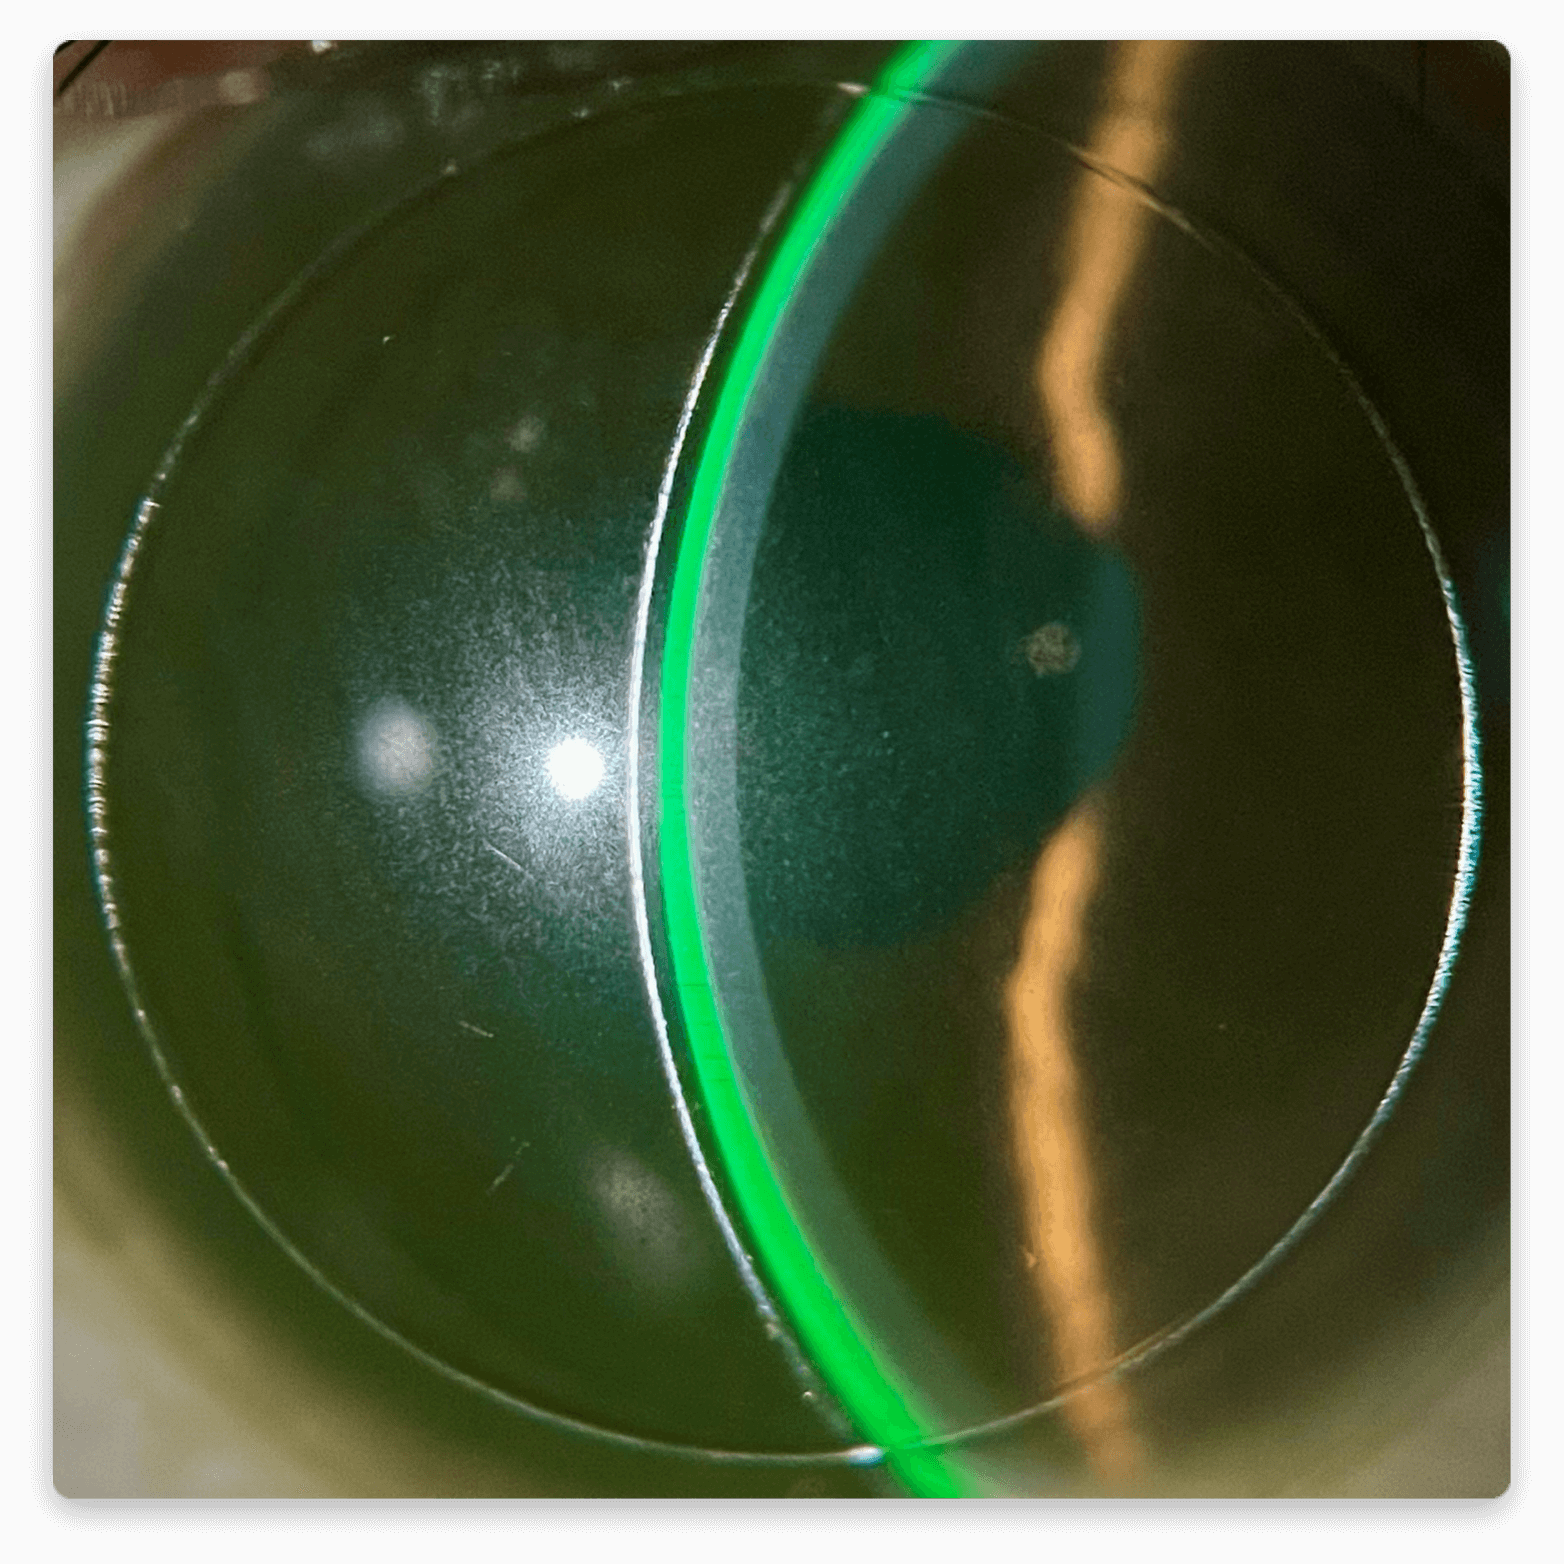

Our Scleral lenses, enables practitioners to tailor the fit across four distinct areas: Central, Intermediate, Peripheral, and Edge. The system accommodates various designs, such as Multifocal, Oblate, Front Toric, Toric Haptic, Quadrant Specific, and Controlled Peripheral Recess (CPR).

These lenses are constructed from materials that allow oxygen to permeate the lens easily and continuously. Their distinctive design corrects vision by eliminating irregularities on the front surface of the eye. Scleral lenses are applied to the eye with a non-preserved saline solution, creating a thin cushion of fluid between the lens and the eye. This cushion enhances comfort, reduces redness, and fosters a healthy environment for the eye.